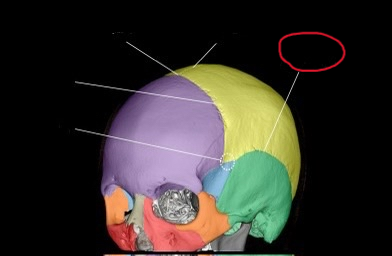

anth 1400 lab exam 1 cranial, skull shit

sphenoid bone (lateral)

also greater wing

frontal bone (lateral)

ethmoid bone (lateral)

also orbital plate

temporal bone (lateral)

occipital bone (lateral)

parietal bone (lateral)

coronal suture (lateral)

pterion

coronal suture (suture)

bregma

sagittal suture

squamosal suture

lambdoid suture